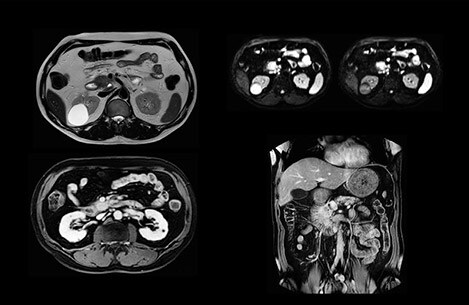

• Ingenia MR-RT XD image serie

MR-only radiotherapy planning